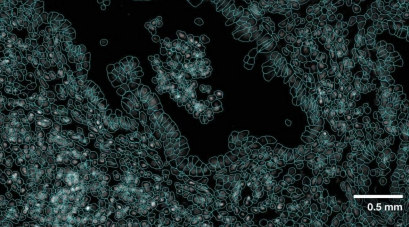

尽管单细胞技术通过评估个体水平上的细胞来帮助研究人员了解疾病,但它们在这些细胞周围的组织内缺乏空间背景。随着空间转录组学的引入,研究人员可以使用从关系数据到成像数据的所有内容来更好地了解基因表达和细胞动力学。

关系数据提供了细胞彼此之间位置位置的上下文,并使成像数据与分子数据叠加成为可能。细胞的定位以及它们在环境中的相互作用对于研究至关重要,尤其是在研究稀有细胞类型时。然而,空间组学提供了比局部细胞相互作用更多的背景,展示了疾病在组织结构中的进展情况。因此,科学家们能够获得罕见细胞类型和疾病进展的以前未知的空间背景。